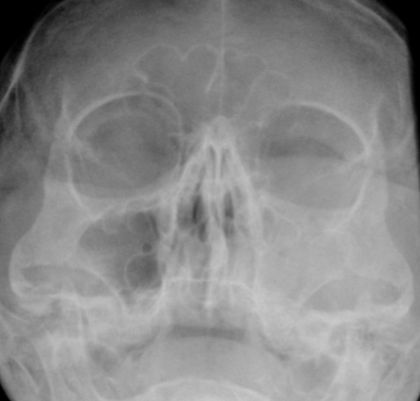

| Röntgen | Normalbefund![]() |

Verschattung der linken Kiefernhöhle nach Gesichtsprellung![]() | |||||||||